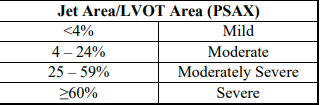

Jet area / LVOT area (PSAX)

mild

moderate

moderatley severe

severe

Jet area / LVOT area (%) (PSAX)

mild

moderate

severe

mild

<4%

moderate

4 - 24%

25 - 59%

severe

>60%